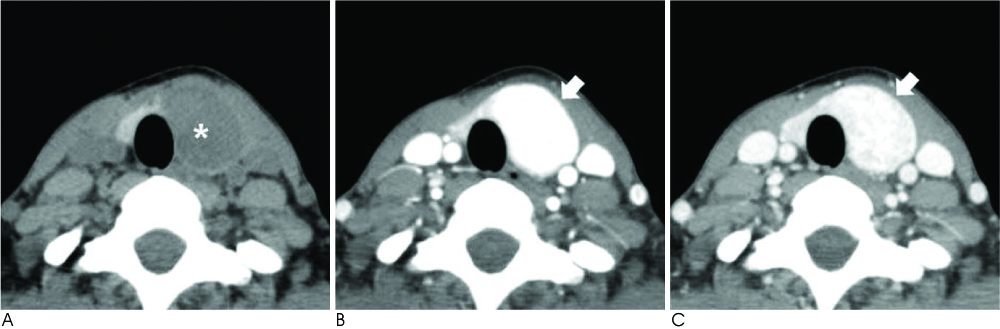

The purpose of this study is to analyze the computed tomography (CT) features of follicular thyroid carcinoma (FTC) as compared to those of papillary thyroid carcinoma (PTC) to identify the characteristic imaging features of FTC.

There were no significant differences between the patients with FTCs and those with PTCs with respect to age and gender, and the internal composition, calcification and enhancement homogeneity of the tumor. However, the FTCs tend to show a larger size (32 mm vs. 15 mm; respectively, p < 0.001), a round to oval shape (52.9% vs. 14.8% respectively, p = 0.001), a well-defined smooth margin (58.8% vs. 14.8% respectively, p = 0.009), less extrathyroidal extension (11.8% vs. 51.9% respectively, p = 0.007) and less LN metastasis (0% vs. 29.6% respectively, p = 0.016) compared to that of the PTCs. Furthermore, the FTCs showed significantly stronger enhancement in the early phase (146.4+/-42.4 vs. 98.5+/-38.2 respectively, p < 0.001) and a greater decrement of the late enhancement (-44.6+/-25.2 vs. -18.7+/-27.9 respectively, p = 0.003) compared to that of the PTCs.

FTCs had a tendency to be observed on neck CT as well-defined, smooth, round to oval nodules with strong early enhancement and a definite decrement of late enhancement as compared to the PTCs.